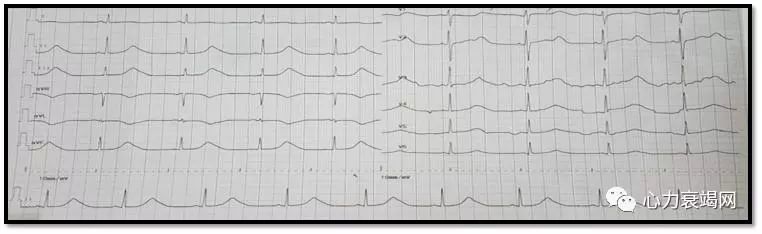

➤ ECG:

窦性心动过缓、QT间期延长(QTc576 ms)